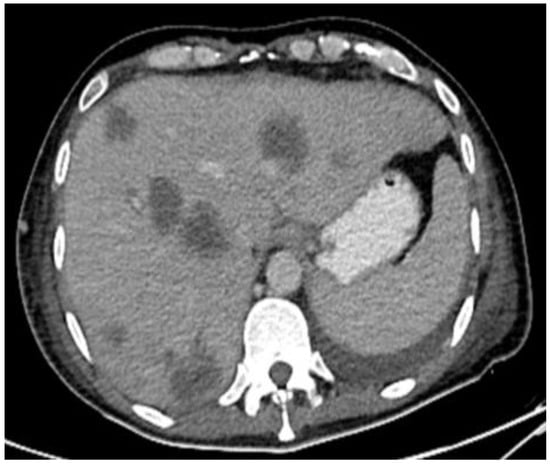

Figure 9.

CT in the axial view of an abdominal window showing liver metastasis.

This plan required alteration, as the patient presented again to the hospital three weeks later with worsening symptoms from persistent priapism. This time he also presented with dyspnea and was found to have undergone rapid disease progression, with imaging evidence of new bilateral lung metastases, hepatic metastases, pelvic and inguinal adenopathy, and pubic bone lytic lesions. He was also found to have developed multiple venous thromboemboli with a high clot burden, including bilateral subsegmental pulmonary emboli and thromboses of the right external iliac, left greater saphenous, and bilateral dorsal penile veins (Figure 3, Figure 4, Figure 5, Figure 6, Figure 7, Figure 8 and Figure 9). In addition, there was increased spiculated soft tissue swelling along the dorsal penile shaft and extensive nodularity in the scrotum and inguinal lymph nodes, suggesting tumour invasion of the reproductive organs (Figure 4, Figure 5 and Figure 6). During the physical examination, the penis, scrotum, and pre-pubic areas were dramatically enlarged and firm, with numerous cutaneous lesions consistent with replacement with a tumour. Urology staff were consulted, and they suggested that the disease was not resectable.

Despite palliative chemotherapy and palliative radiation, the patient’s clinical status continued to deteriorate. He developed worsening lethargy, poor intake, renal failure, and open penile and scrotal sores with purulent drainage, indicative of a superimposed infection, and he was re-admitted for further management. Imaging showed the significant further progression of metastatic disease (Figure 7, Figure 8 and Figure 9), especially in the pelvis, with new bilateral hydroureteronephrosis and evidence of ileus. He was deemed to no longer be a candidate for further radiation or systemic therapy because of his declining clinical condition. The urology staff again recommended against the resection of the scrotum and penis. He elected to pursue comfort measures only and died in hospital.